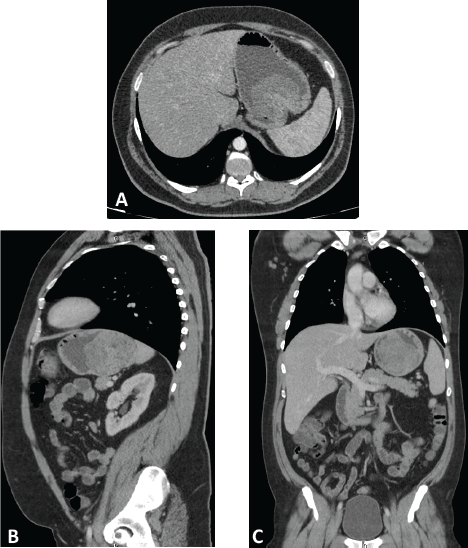

A computed tomography (CT) scan was performed, showing a highly vascularised tumour with an endophytic growth in the upper gastric body measuring 90 × 89 × 70 mm (Figure 1). No distant metastases were seen.

Figure 1. Computed tomography with intravenous and oral contrast. Axial (A), parasagital (B) and coronal (C) planes showing a highly-vascularized tumor with an endophytic growth in the upper gastric body measuring 90 x 89 x 70 mm.